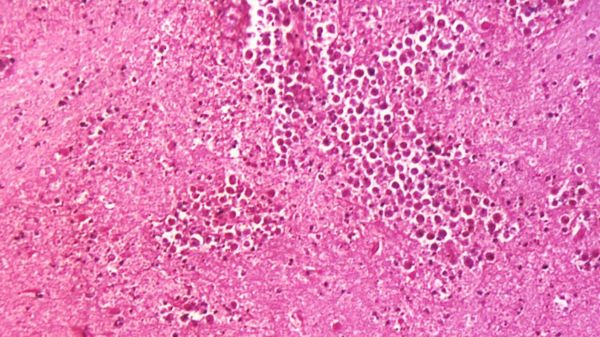

Попав в нос, паразит Неглерия Фоулера (Naegleria fowleri) по обонятельному нерву добирается до мозга и поражает мозговую ткань. При этом, как отмечают медики, пить зараженную бактерией воду не опасно. Главное — чтобы она не попала именно в нос.

Официальное название болезни, вызываемой этим одноклеточным микроорганизмом, — первичный амебный менингоэнцефалит.